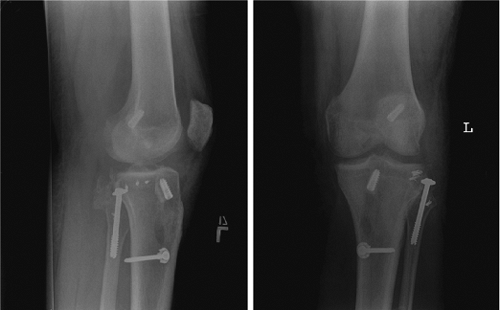

tensioning and fixation can be accomplished in the following stepwise

manner: Our preference is first to tension and fix the PCL, then the

ACL, followed by the lateral structures, and finally the medial

structures. The PCL is fixed distally with the knee in 90 degrees of

flexion, and a bolster is placed under the tibia to support its weight

against gravity. While the assistant is performing anterior drawer, the

graft is fixed distally with an interference screw and/or a 4.5-mm AO

screw and washer via standard post fixation. The ACL graft is tensioned

and fixed distally in full extension with

an

interference screw or a screw and washer. The knee is maintained in 30

degrees of flexion for fixation of both the PLC and LCL grafts. The PLC

is reduced and fixed with an internal rotation force applied to the

tibia relative to the femur. The MCL is fixed in 30 degrees of flexion.

(Figs. 25.12,25.13,25.14).

Figure 25.12. Postoperative radiographs of ACL/PCL/LCL reconstruction with PLC primary repair.

Figure 25.13. Postoperative radiographs of ACL/PCL/MCL reconstruction.

Figure 25.14. Postoperative radiographs of ACL/PCL/PLC reconstruction.